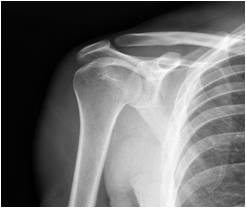

Anatomy of the shoulder joint

The shoulder is a ball and socket joint formed by the arm bone (humerus) and the shoulder blade (scapula).